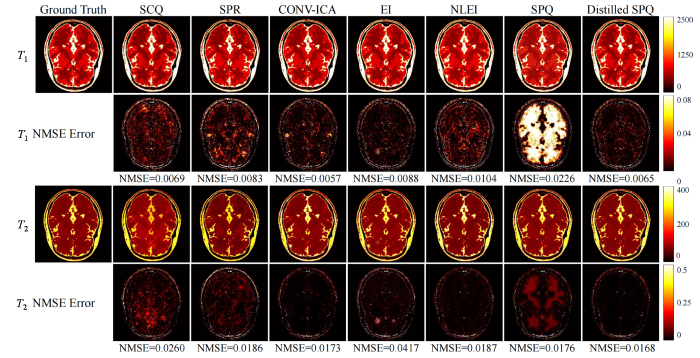

图7 展示了BrainWeb测试集中一组数据经不同方法重建的定量参数图.每一列从左至右依次为基准参数图、SCQ、SPR、CONV-ICA、EI、NLEI、仅采用本文中提出的基础自监督参数量化网络SPQ和结合知识蒸馏框架的自监督参数量化网络distilled SPQ重建出的参数图.第一行与第三行分别呈现T 1 与T 2 参数图重建结果,第二行与第四行则为对应的归一化均方误差分布图.第二、四行下方数值表示对应误差图的均值统计结果.实验在200长度短帧数据下进行,由于缺乏足够的时域组织判别特征,作为对比的有监督和无监督参数量化方法尤其是EI方法的量化结果在局部区域出现较大偏差,这对于患者病灶部位成像非常不利.相比之下,本文提出方法通过引入包含长帧数据下教师模型的知识蒸馏框架,具有较好的量化表现.

图7

基于一组200长度BrainWeb测试数据的不同方法参数量化结果对比

Fig. 7

Comparison of parameter quantification results of different methods based on a set of 200-length BrainWeb test data